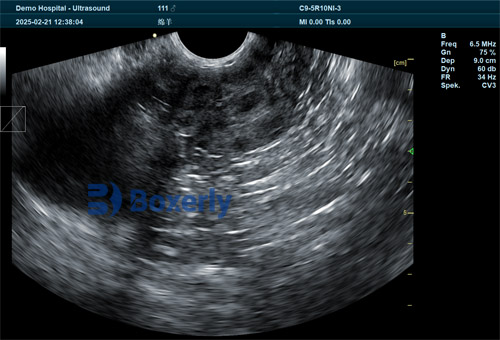

Ultrasound images during this stage typically show a gestational sac first (day 19–22), followed by clearer yolk sac visualization (day 22–28). Both structures are best observed between days 24–26. Beyond this window, the yolk sac begins to shrink and becomes harder to detect, while the gestational sac gets gradually replaced by the developing pregnancy cavity.

This stage marks a transition in the visible uterine contents. By around day 26, the developing pregnancy cavity begins to dominate the image. Detection rates rise sharply from day 27 to 31—the primary growth phase—and continue at a slower pace from day 32 to 37.

Between days 32–37, the pregnancy cavity is at its most distinguishable. However, after day 37, a new pattern emerges. The visualization of placental and fetal structures increases rapidly, making pregnancy cavity signs less distinct. In practice, this means that while detection is still possible, the focus of the scan shifts toward fetal viability and development rather than simple confirmation.

During days 40–43, placental visualization dominates, with fetal structures becoming more prominent after day 43. Heartbeats, limb movements, and cranial formations are often visible during this stage, offering not just confirmation of pregnancy, but also information on fetal viability.